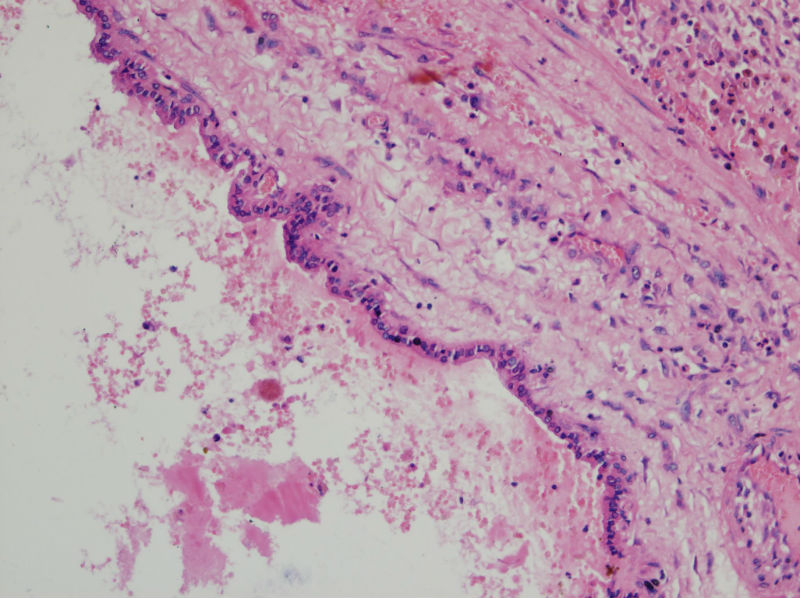

男,44,甲状腺囊肿.直径1.5公分,内流清亮液

• 甲状腺囊肿,请老师们指教图1

图1

结节性甲状腺肿伴出血、囊性变。囊肿边上的滤泡大小不一,纤维组织增生,还可见炎细胞浸润。